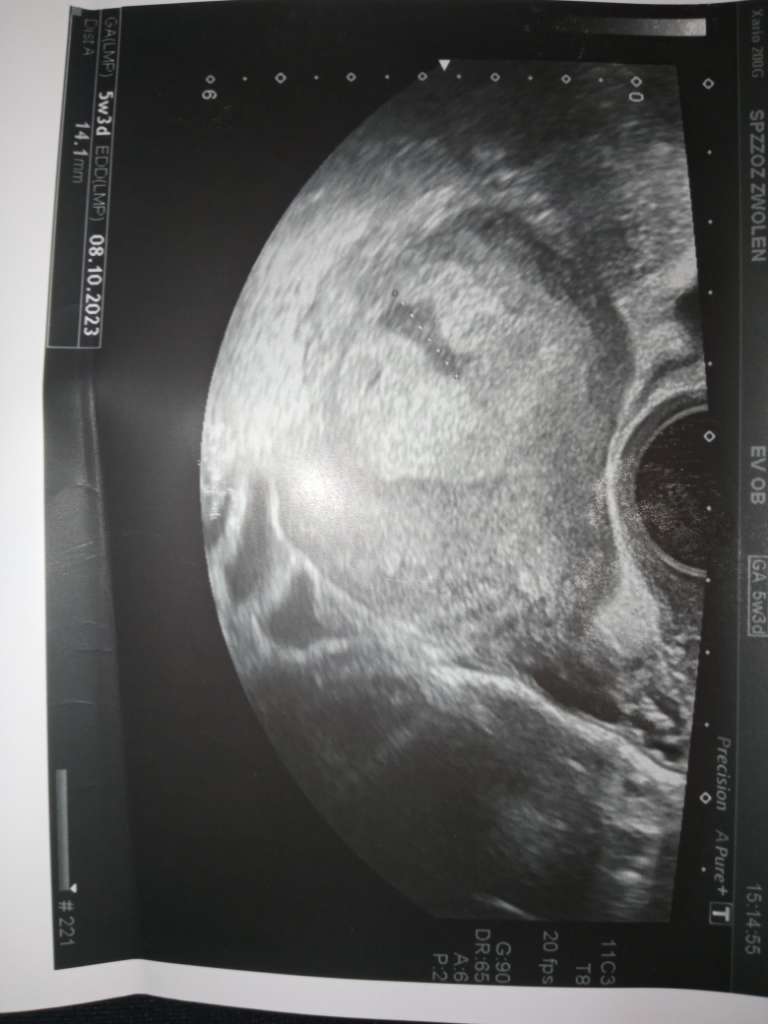

Cześć byłam dziś na wizycie u ginekologa wyszło że jestem jakoś w 5 tyg i 3 dni, lekarz zobaczył na USG taką jakby zatoczkę jest ona na pierwszym zdjęciu i przepisał mi duphaston bo uważa że to łożysko się zaczyna odklejać... Kazał się oszczędzać, będzie ciężko patrząc na to że mam dwuletnie dziecko w domu. Powiedziałam mu też że mam bóle podbrzusza. Wiem że nie jesteście lekarzami, ale na tym USG serio to tak wygląda ? Chodzi o tą jakby plamkę co jest pod tym całym łożyskiem, boje się że coś się stanie.

znaczy po prostu nie będę go brała na ręce, tak to nie jest mały aż taki zły haha dokucza trochę. Właśnie myślę czy mi dał to przez tą plamę czy przez to że mu powiedziałam że mnie boli podbrzusze trochę, ale on spojrzał na USG i powiedział że to wygląda tak jakby groziło poronienie właśnie przez tą plamkę...

szczerze mówiąc to już sama nie rozumiem... Mówił po prostu że ciąża moze się nie utrzymać bo to wygląda jakby się odklejało...